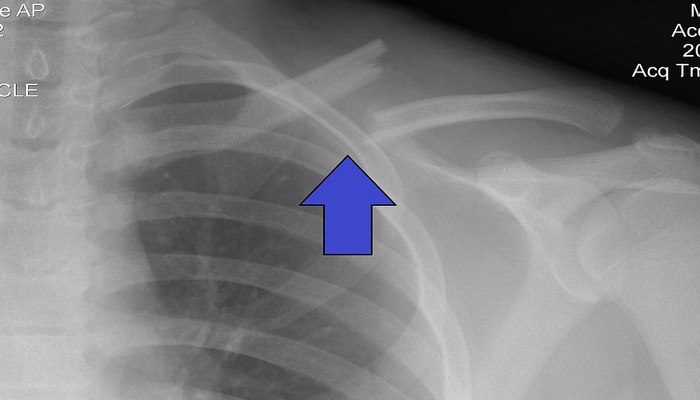

Körpücük sümüyünün sınıqları

Körpücük sümüyünün sınıqları — çiyinə olan bir başa və ya dolayısı ilə olan travma nəticəsində baş verir.

Travma nəticəsində baş verən sınıqlar sırasında körpücük sümüyü sınıqları təxminən 2.6% hallarda müşahidə edilir. Bu sınıqlar daha çox uşaq və gənclərdə müşahidə edilir. Körpücük sümüyü sınıqlarının üçdə biri 13-20 yaş arasında olan xəstələrin payına düşür. 20 yaşdan sonra körpücük sümüyü sınıqlarının sayı azalmağa doğru gedir və yenidən ahıllıq dövründə artmağa başlayır. Bir sıra araşdırmalardan bəllidir ki, körpücük sümüyü sınıqlarının təxminən 69% sümüyün orta 1/3 hissəsinə, 28%-i distal 1/3 hissəsinə və 2.8%-i isə proksimal 1/3 hissəsinə düşür. Distal 1/3 hissənin sınıqları öz növbəsində 3 tipə bölünür. Məhz sınığın lokalizasiyası körpücük sümüyü sınıqlarının təsnifatının əsasını təşkil edir.